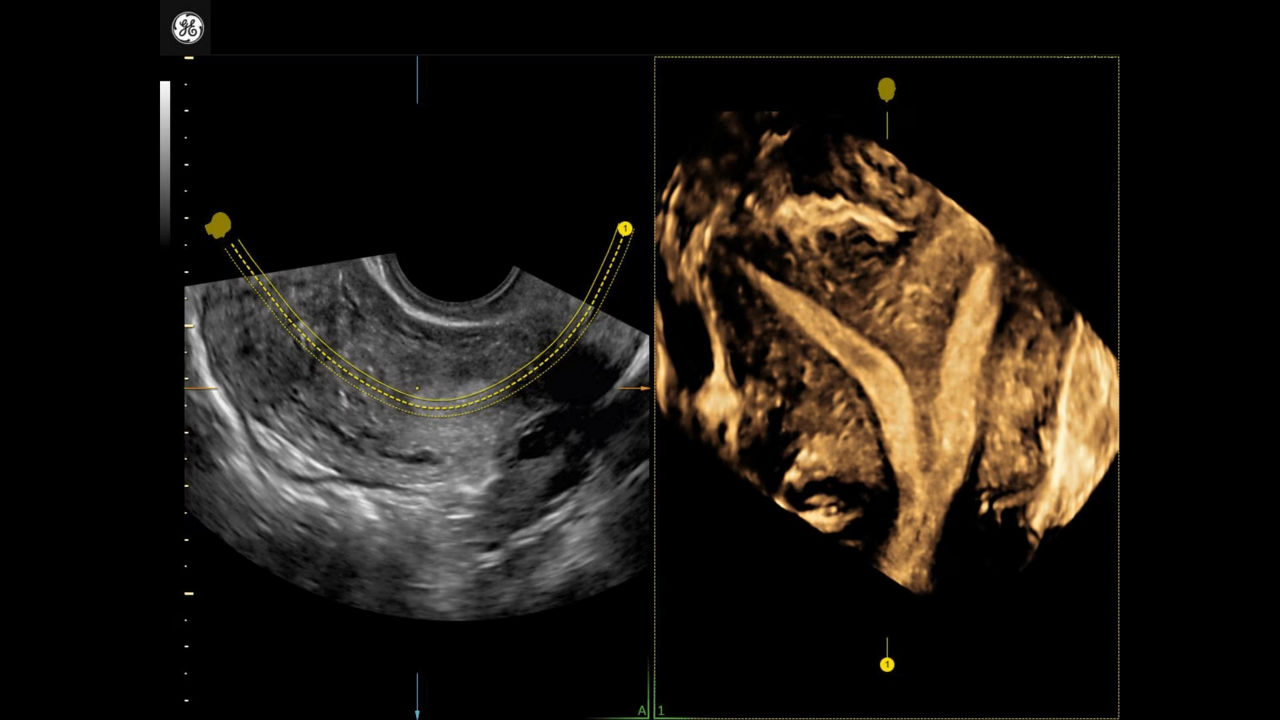

Uterine Trace

Easy display coronal view of uterus

Developed by: GE HealthCare - Voluson™

1_uterine-trace-septate-uterus